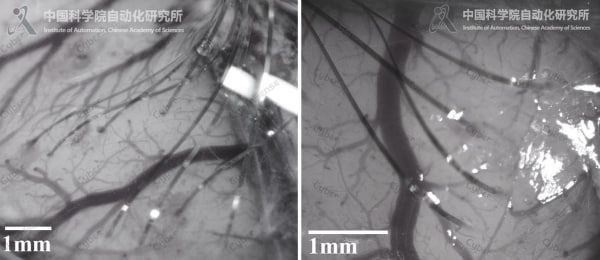

🌐 ΠšΠΈΡ‚Π°ΠΉΡΠΊΠ°Ρ акадСмия Π½Π°ΡƒΠΊ прСдставила Ρ€ΠΎΠ±ΠΎΡ‚Π° CyberSense, способного с высокой Ρ‚ΠΎΡ‡Π½ΠΎΡΡ‚ΡŒΡŽ Π²ΠΆΠΈΠ²Π»ΡΡ‚ΡŒ Π² ΠΌΠΎΠ·Π³ ΠΆΠΈΠ²ΠΎΡ‚Π½Ρ‹Ρ… Π³ΠΈΠ±ΠΊΠΈΠ΅ микроэлСктроды, Ρ‚ΠΎΠ½ΡŒΡˆΠ΅ чСловСчСского волоса. Π­Ρ‚ΠΈ ΠΈΠΌΠΏΠ»Π°Π½Ρ‚Π°Ρ‚Ρ‹ Π½Π΅ Ρ‚ΠΎΠ»ΡŒΠΊΠΎ ΡΡ‡ΠΈΡ‚Ρ‹Π²Π°ΡŽΡ‚ Π½Π΅ΠΉΡ€ΠΎΠ½Π½ΡƒΡŽ Π°ΠΊΡ‚ΠΈΠ²Π½ΠΎΡΡ‚ΡŒ, Π½ΠΎ ΠΈ ΠΌΠΎΠ³ΡƒΡ‚ ΡΡ‚ΠΈΠΌΡƒΠ»ΠΈΡ€ΠΎΠ²Π°Ρ‚ΡŒ ΠΌΠΎΠ·Π³ с ΠΏΠΎΠΌΠΎΡ‰ΡŒΡŽ ΠΌΠΈΠΊΡ€ΠΎΡ‚ΠΎΠΊΠΎΠ², открывая ΠΏΡƒΡ‚ΡŒ ΠΊ Π½ΠΎΠ²Ρ‹ΠΌ ΠΌΠ΅Ρ‚ΠΎΠ΄Π°ΠΌ лСчСния, ΡƒΠΏΡ€Π°Π²Π»Π΅Π½ΠΈΡŽ внСшними устройствами силой мысли ΠΈ Π³Π»ΡƒΠ±ΠΎΠΊΠΎΠΌΡƒ ΠΈΠ·ΡƒΡ‡Π΅Π½ΠΈΡŽ Ρ€Π°Π±ΠΎΡ‚Ρ‹ ΠΌΠΎΠ·Π³Π°.